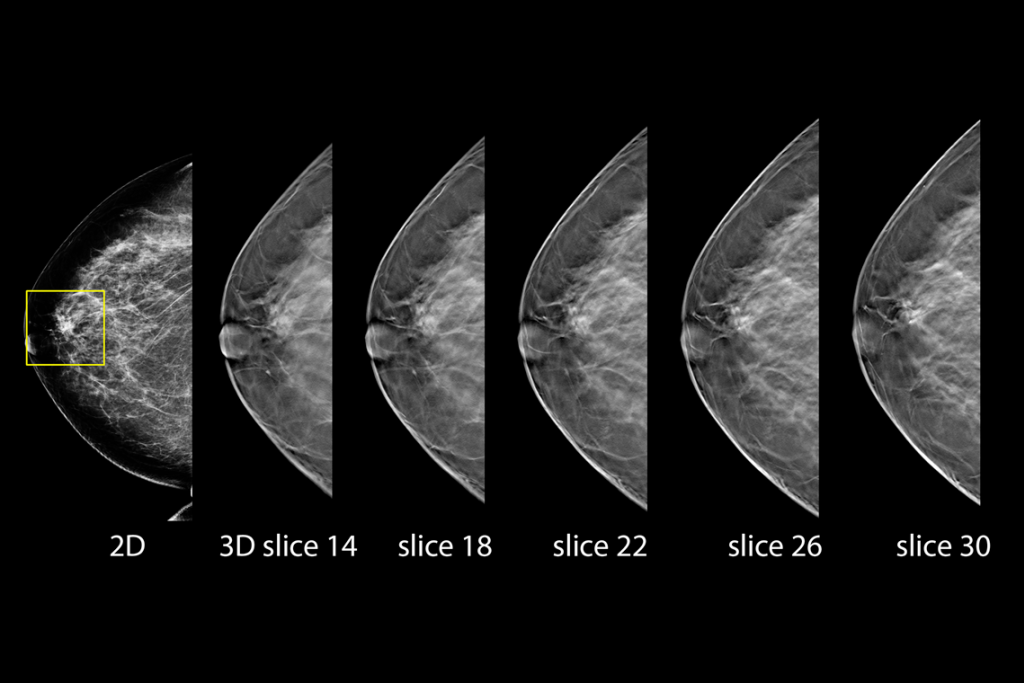

乳房検査の臨床画像

脂肪性乳房の乳房検査の臨床画像